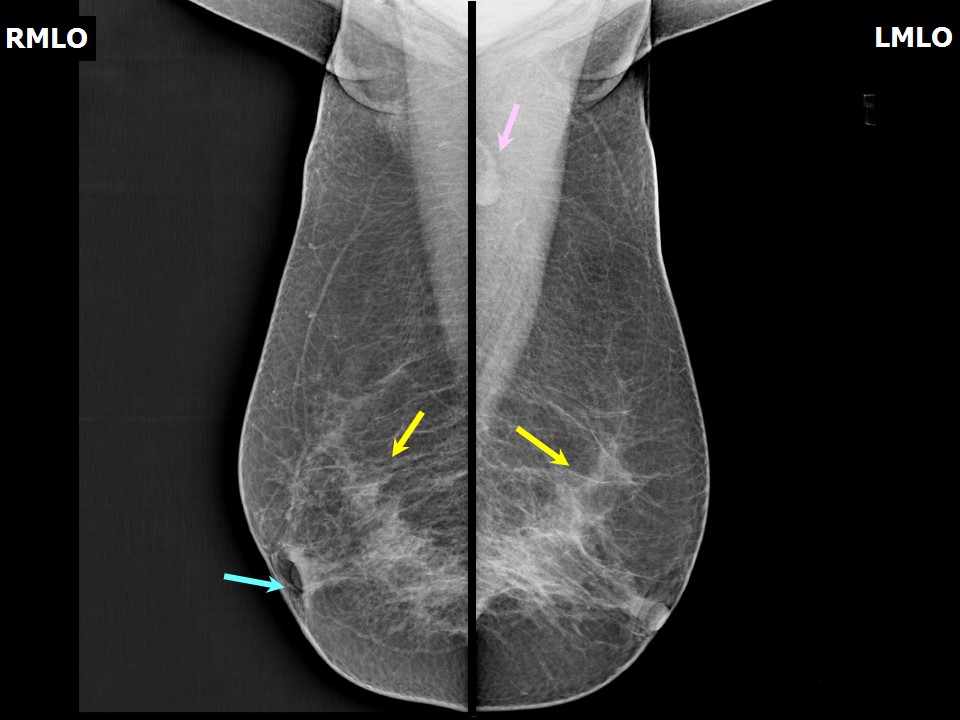

Феномен гипердиагностики в маммографии: примеры и иллюстрации

Раздел: Образы вокруг